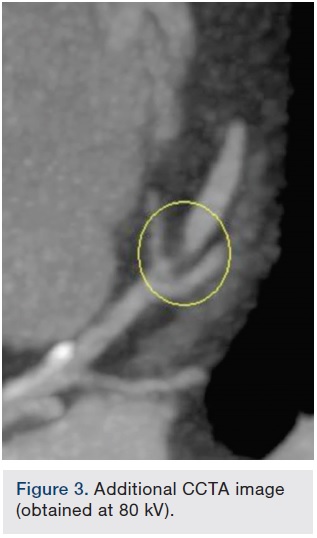

The SOMATOM Force CT system (Siemens Healthcare), which enables fast temporal resolution, was used to perform a coronary CT angiogram (CCTA) on an emergency department patient. The CCTA displayed a 90 percent or greater non-calcified short stenosis in the mid left anterior descending coronary artery (LAD). The next day, the patient’s coronary catheterization revealed a mid-LAD stenosis, type B1 and ulcerative, just distal to a moderate-sized diagonal. A drug-eluting stent was placed; no residual stenosis and normal distal flow was observed. A day after stent placement, the patient was discharged.

Images/courtesy St. Elizabeth Hospital, Edgewood, Kentucky